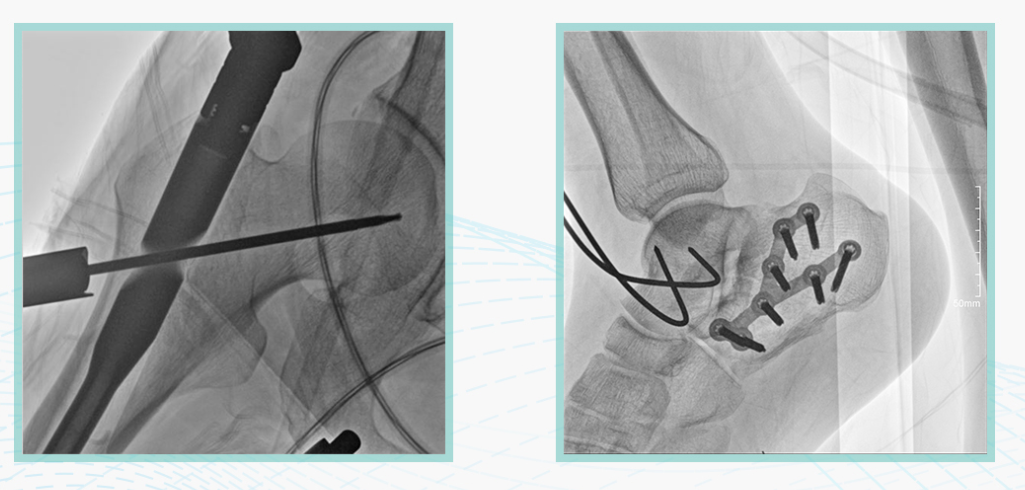

此外,骨科手術時間平均時長約為45分鐘左右時間,長期的X線透視或攝影曝光劑量將對臨床手術與操作醫務工作者造成難以評估的健康風險,悅畫通過支持攝影曝光參數的自主調節,可以保證在最低劑量水平下輸出滿足臨床手術定位與引導所需要的影像質量,相較于市面上的固定曝光參數配置移動C臂,自主參數調節設計的曝光功能設計,可以大幅減少醫務工作者的X線輻射劑量。

不僅如此,悅畫在產品的劑量安全管理上,還支持DAP劑量實時顯示與統計功能。為了減少誤操作的X射線曝光,悅畫具有X射線鎖定保護功能,在攝影曝光停止后立即進行X射線曝光鎖定,解鎖后才能支持繼續曝光,減少以往臨床過程中醫務工作者因為誤操作所導致的額外X射線輻射。